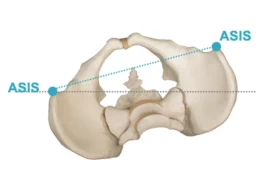

فعندما لا يتحرك مفصل الفخذ الأيمن بحرية كافية، يميل الحوض إلى أحد الجانبين. هذا الميل يجعل الساق اليمنى تبدو أطول من اليسرى، فيميل الجسم لتعويض الفرق في الطول. ومع الوقت يبدأ العمود الفقري في الانحناء للمحافظة على التوازن.

يميل الحوض تدريجيًا نحو الأعلى في جهة، وإلى الأسفل في الجهة المقابلة.